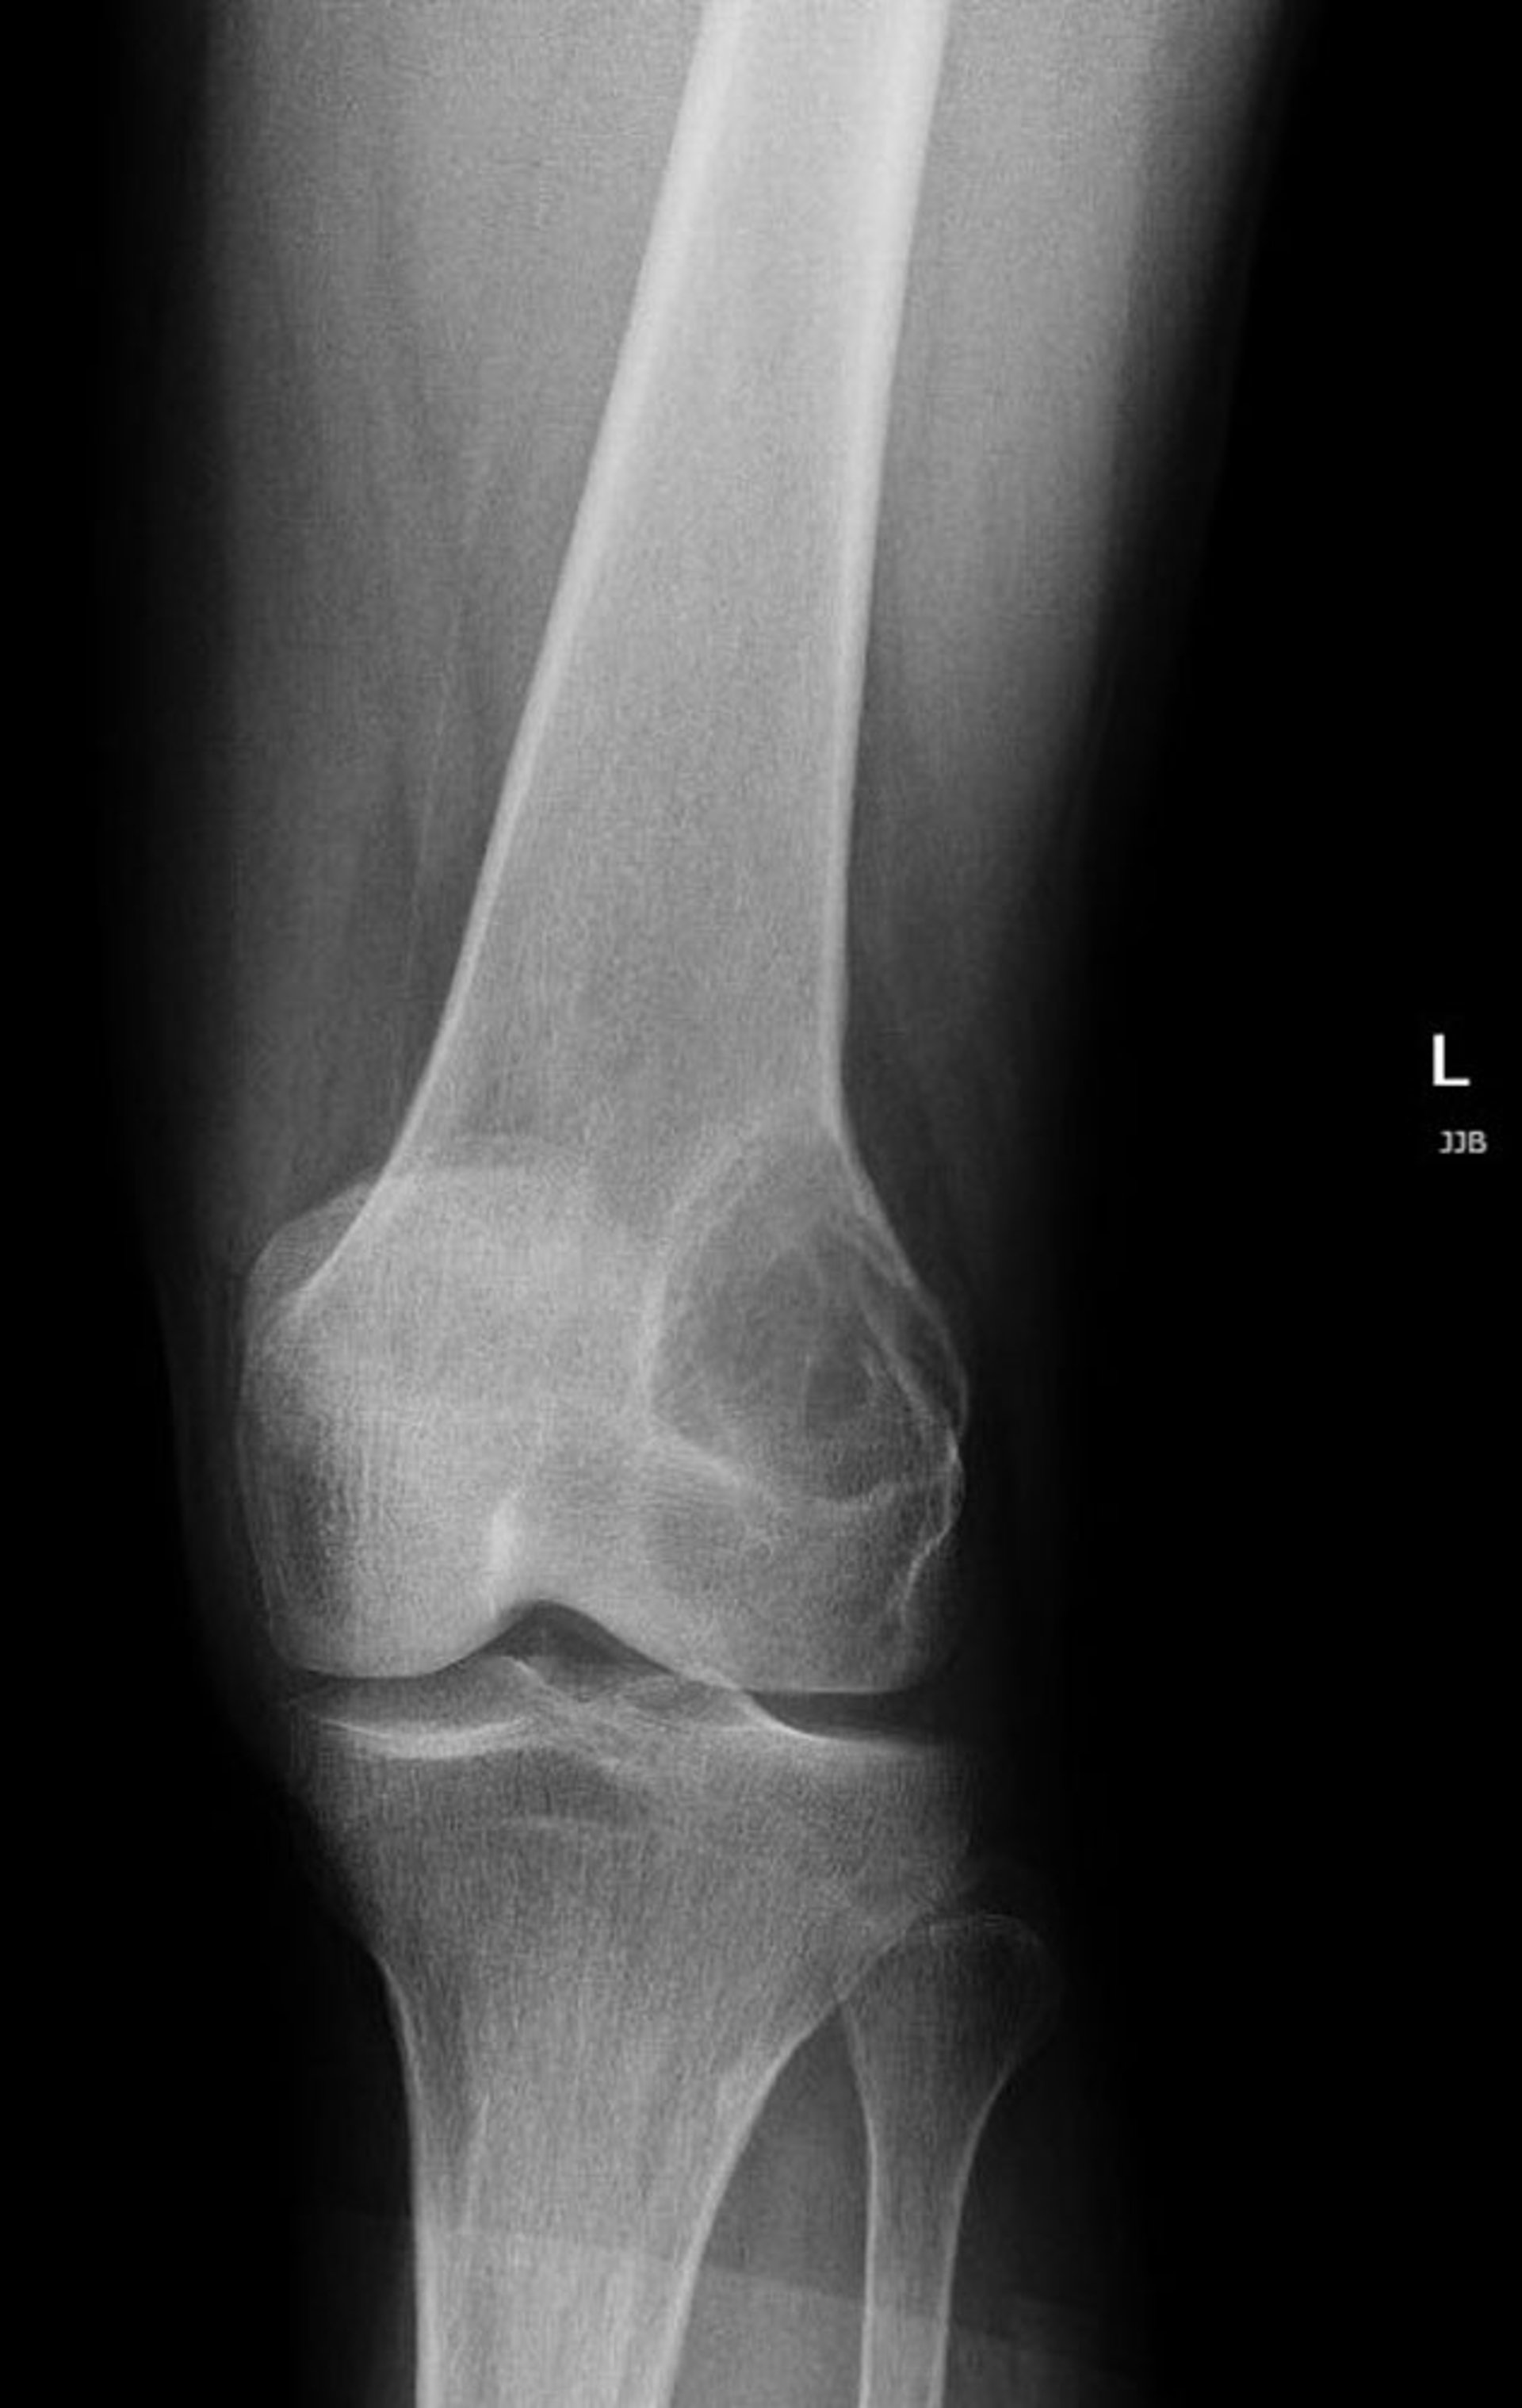

This radiograph of the knee shows a radiolucent lesion in the lateral distal femur above the knee, which is characteristic of a giant cell tumor of bone.

Image courtesy of Lukas Nystrom, MD.